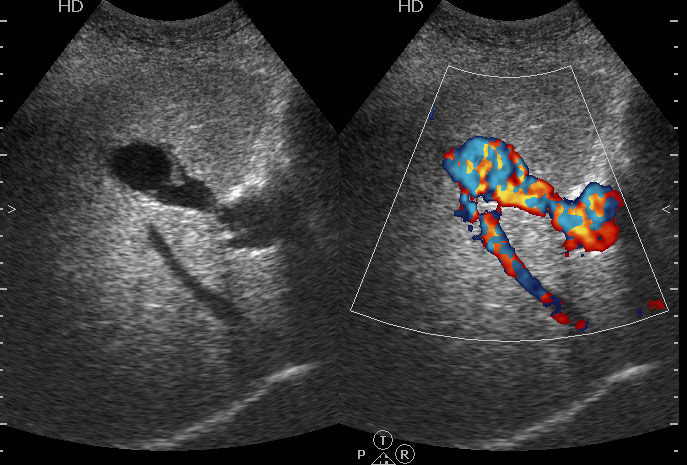

УЗИ: портосистемный внутрипеченочный шунт

Больная с с желтухой, направлена на УЗИ для уточнения ее причины. Никих операций до обращения в стационар не было.